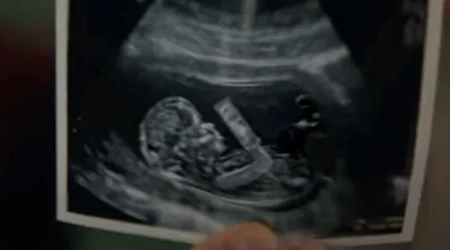

Por eso cada 25 de marzo se celebra en España la Jornada por la Vida, que este año se realiza bajo el lema "Contigo por la vida, siempre". No obstante, denuncia Mons. Fernández, "continúa el chorro de abortos a diario en nuestro entorno".

El Prelado censura que "se subraya el derecho de la madre a eliminar a su hijo en el seno materno y no se tiene en cuenta el derecho del que va a nacer; la vida se desprecia y se elimina violentamente, hasta llegar a considerarlo un derecho progresista".

Sin embargo, añade el obispo, "no puede haber progreso cuando incluye la matanza de miles, de millones de inocentes". Por eso, anima a estar atentos y salir "al encuentro de personas tentadas al aborto. Es una profunda desgracia de nuestro tiempo".